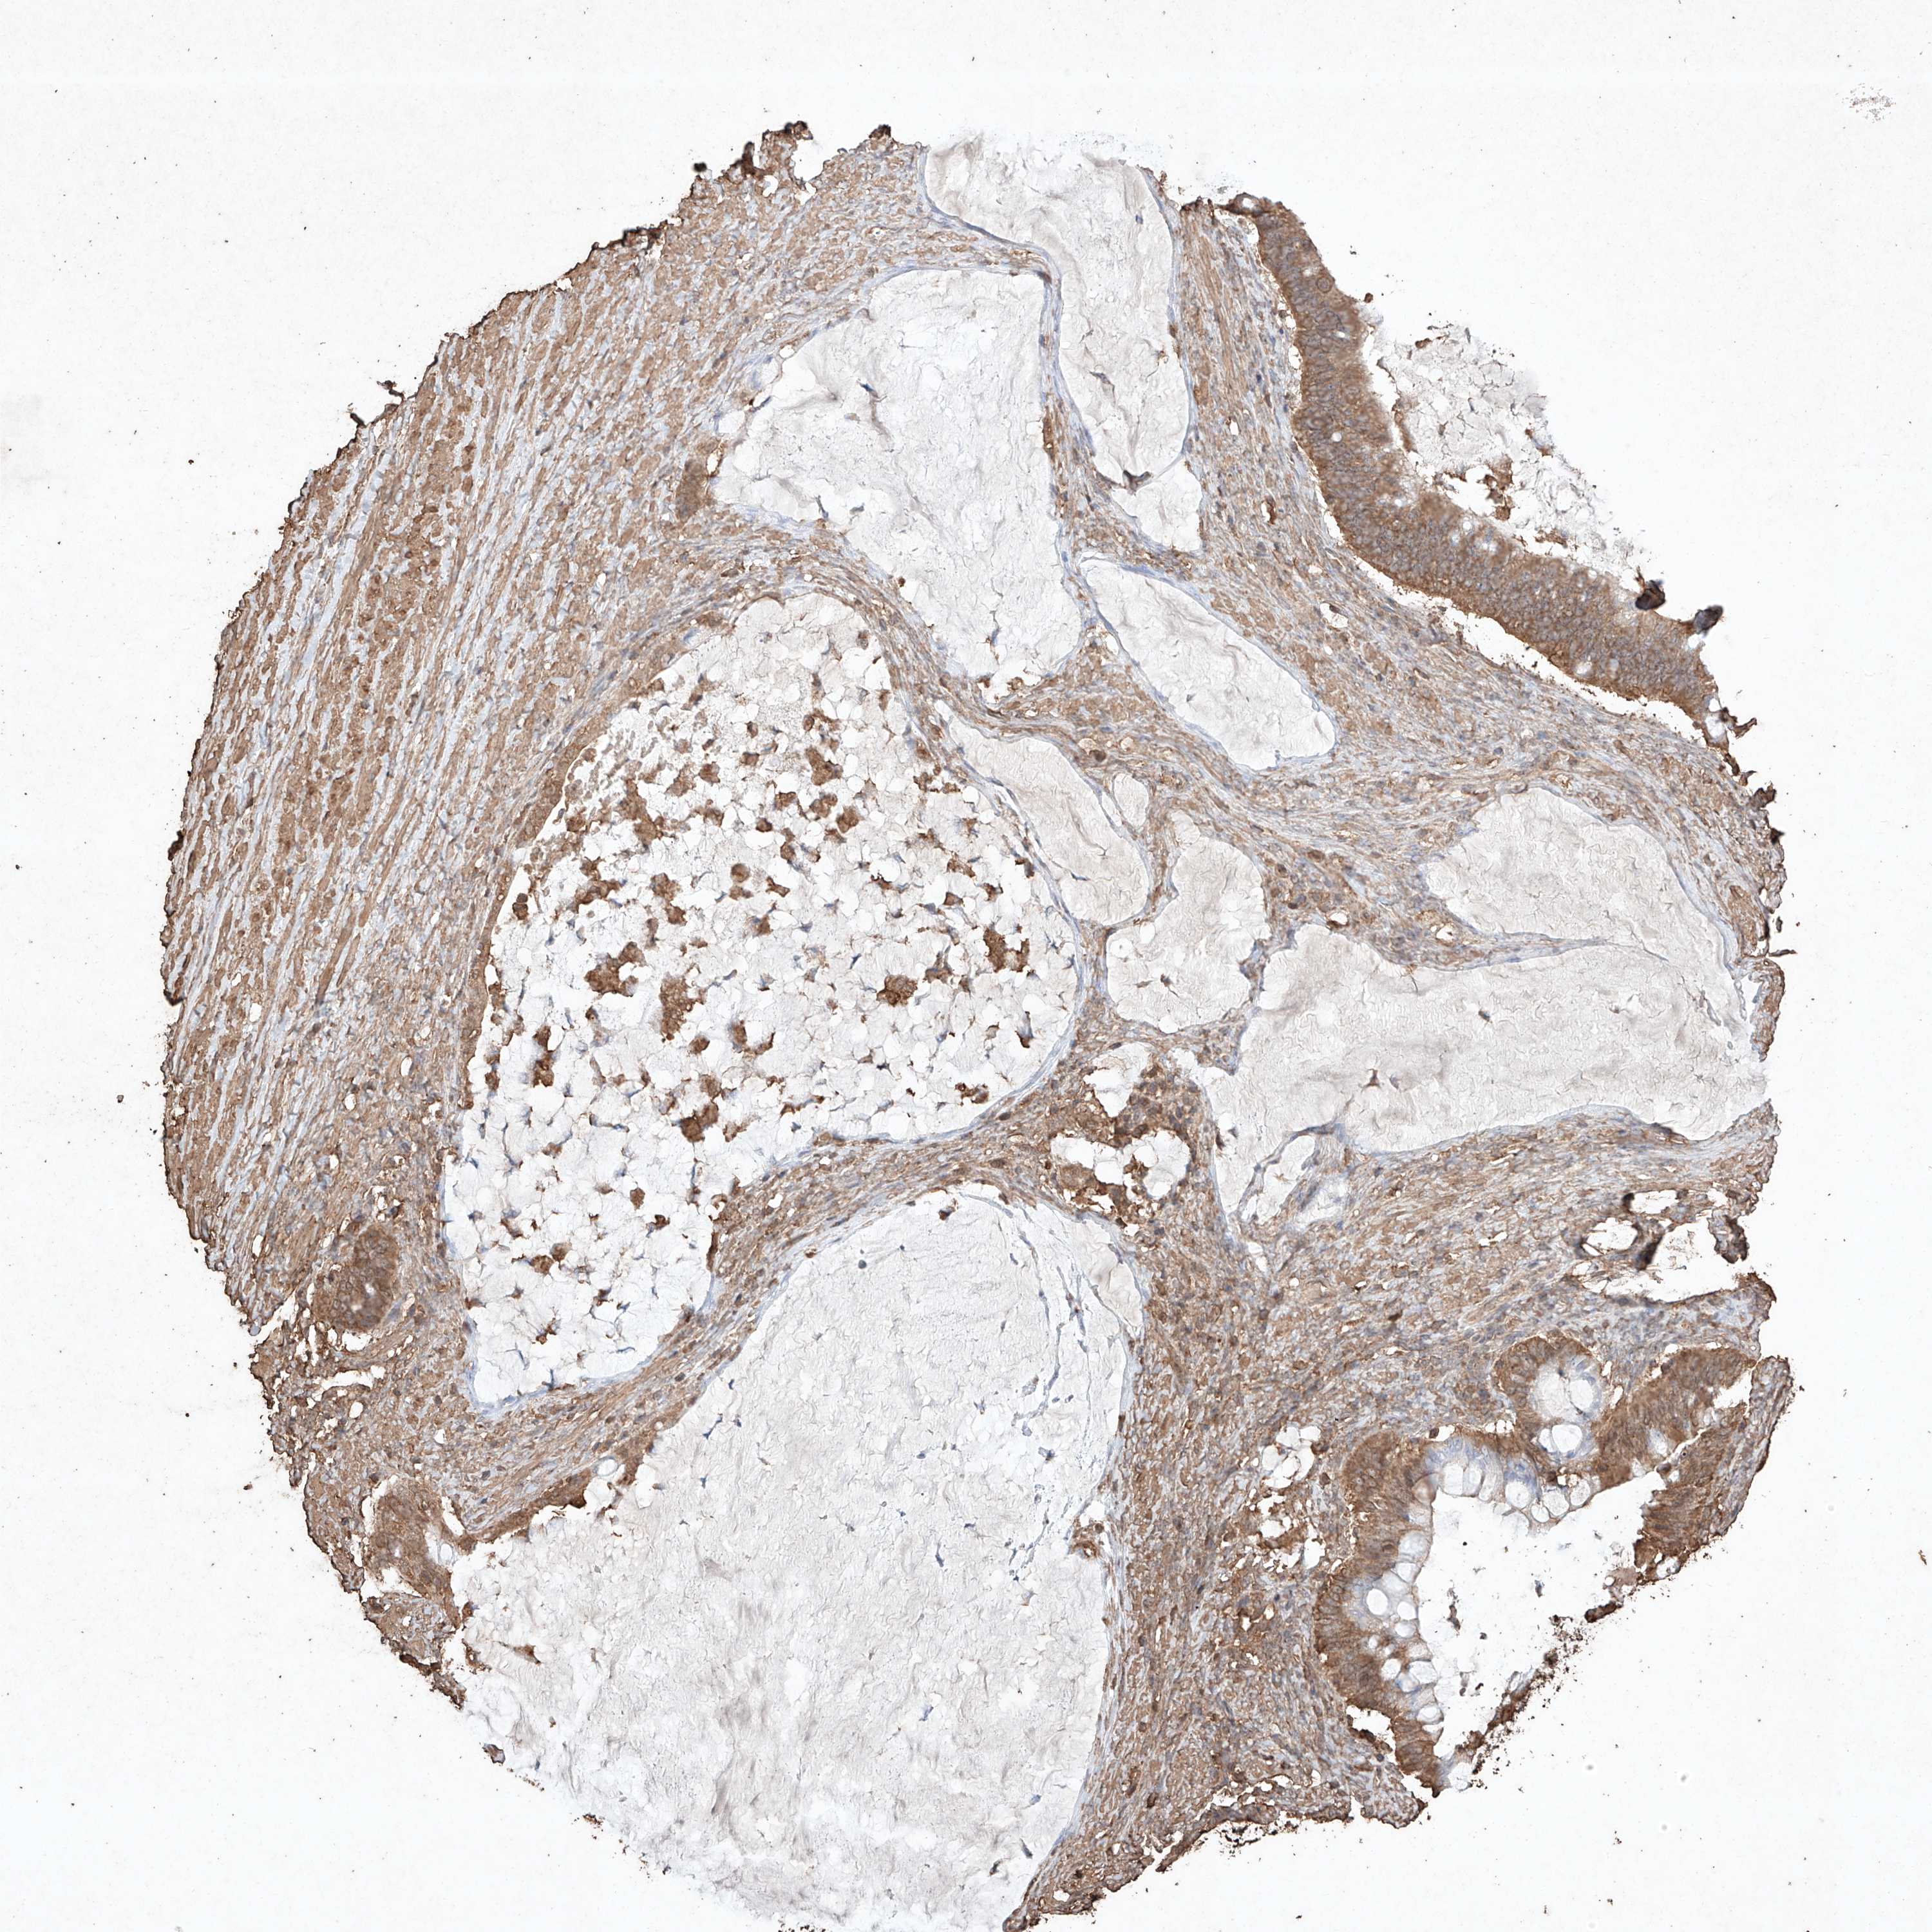

OVARIAN CANCER - Protein expressioni

A mouse-over function shows sample information and annotation data. Click on an image to view it in a full screen mode. Samples can be filtered based on level of antibody staining by selecting one or several of the following categories: high, medium, low and not detected. The assay and annotation is described here.

Note that samples used for immunohistochemistry by the Human Protein Atlas do not correspond to samples in the TCGA dataset.

Antibody stainingi

Antibody staining in the annotated cell types in the current human tissue is reported as not detected, low, medium, or high, based on conventional immunohistochemistry profiling in selected tissues. This score is based on the combination of the staining intensity and fraction of stained cells.

Each image is clickable and will lead to virtual microscopy that enables deeper exploration of all samples and also displays staining intensity scores, fraction scores and subcellular localization as well as patient and tissue information for each sample.

Antibody HPA040445

Antibody CAB034464

Cystadenocarcinoma, serous, NOS

Carcinoma, endometroid

Cystadenocarcinoma, mucinous, NOS

Carcinoma, NOS